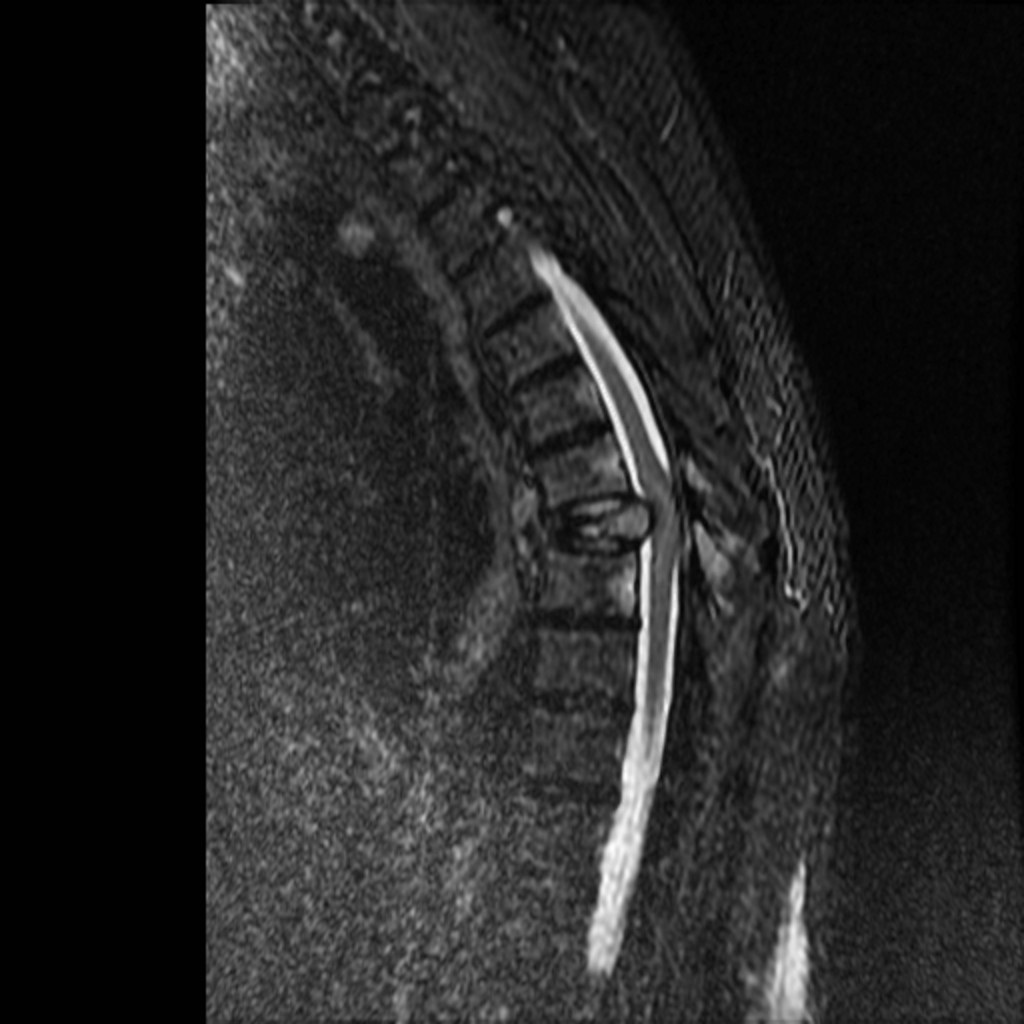

A 63 you male presents with back pain and lower extremity weakness, no bowel or bladder dysfunction. He has midline back tenderness and 4/5 strength in lower extremities. His MRI is shown. What's the diagnosis?

Answer: T8 pathologic fracture in this patient with plasma cell dyscrasia. MRI shows fracture with retropulsion, canal stenosis, spinal cord compression and cord edema.